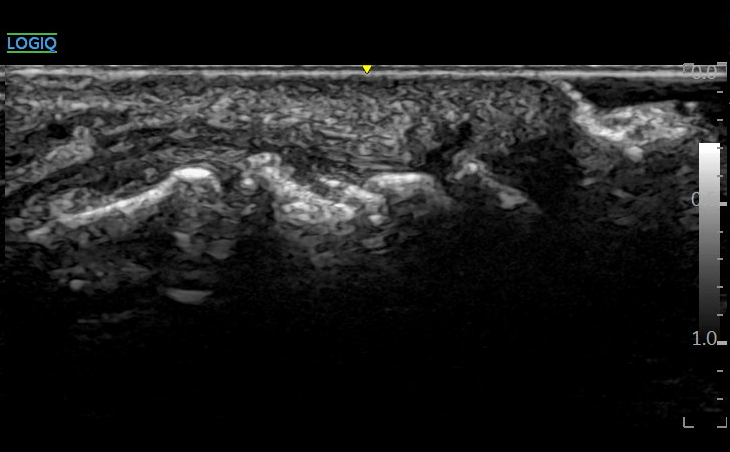

원래 표준 경혈 초음파상

뼈 표면(골 피질, Cortex)이

연결되어 보여야 하는데요.

Step-off sign

네번째 발가락 골피질이 어긋나서 fracture of 4th middle phalanx

솟아오른 모습입니다.

다친 지 4주가 넘었는데

뼈 주변 골막 아래

피가 고여 있고(Hematoma)

주변 조직이 염증으로 부어있습니다.

위쪽 표준 경혈 초음파와 비교해보면

확연히 다른게 보이시죠?